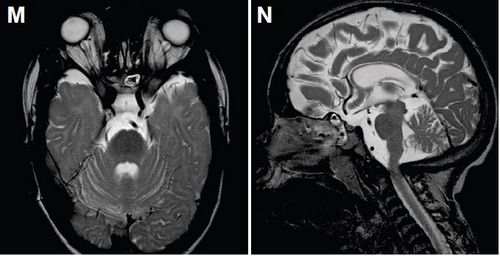

July 24, 2020Molecular cause of disease sparks hopes for severely disabled childrenThe genetic origin of a previously-unrecognized syndrome leading to severe, multiple disabilities in children reveals a potential opportunity for treatment.